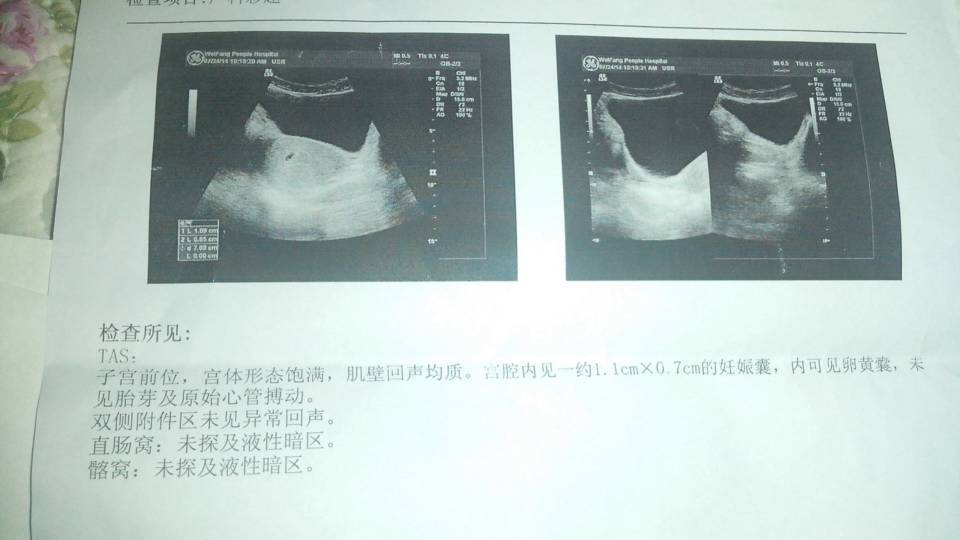

我媳妇现在体内孕酮量降低,下面还伴随着流血,现在很是着急,应该怎么办?